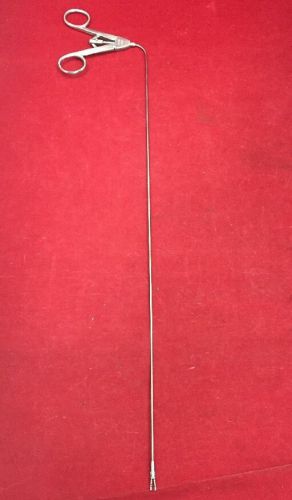

US $64.99

| Condition | Used

An item that has been used previously. The item may have some signs of cosmetic wear, but is fully operational and functions as intended. This item may be a floor model or store return that has been used. See the seller’s listing for full details and description of any imperfections.

| Seller Notes | “No defects, scratches or wear to comment on. These tools have been cleaned correctly and immediately after each use.” |